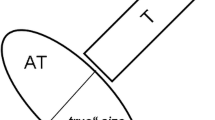

The diagnosis of an enlarged calcaneal tuberosity (Haglund exostosis) on sagittal T1‑w SE images is made by drawing parallel pitch lines on the upper and lower aspects of the calcaneus on sagittal images (Fig. 2c) as described in the literature. In cases of Haglund’s disease, a portion of the tuberosity is seen above the upper pitch line [1, 12].

Case example of a 51-year-old female patient with pain in the AT for 2 months. The maximum thickness of the AT from anterior to posterior, perpendicular to the coronal axis of the AT, on the axial T2‑w image (a; double-headed arrow), was 9.7 mm (20 points). Furthermore, the patient presented with a partial tear (10 points) and fluid-like signal intensity (0 points; long arrow) on the sagittal PD‑w TSE image (b). Associated pathologies (20 points): no Haglund exostosis (minus 0 points; parallel lines (c)), no calcaneal bone marrow edema or cysts (b) but an ossification at the tendon insertion area (–5 points; star) on the T1‑m sagittal image (c); no edema of Kager’s fat pad but slight signal increase along the AT indicating a peritendinitis (b) (–5 points; small arrows); positive retrocalcaneal bursitis (b) (–5 points; curved arrow). Total VIMAT score = 35 points